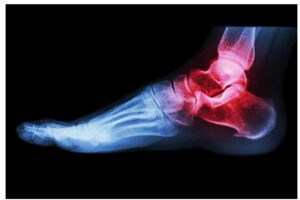

כאבי מפרקים ברגליים

ישנם מקרים בהם תרגישו דלקת

באחת מכפות הרגליים או בשתי הרגליים.

זה יכול להיות תוצאה של סיבות שונות

כמו תוצאות של תאונה איומה כלשהי

או שימוש מופרז בכפות הרגליים שלך בחוסר רגישות.

עם זאת, זה גם כן קשור למחלת דלקת פרקים.

בדלקת מפרקים בכף הרגל,

רקמות וגידים בכף הרגל שלך ייפגעו מסיבה מסוימת

ולא יאפשרו לך לזוז בקלות ובנוחות.

טיפול עם משכך כאבים יכול להקל במצב זה.